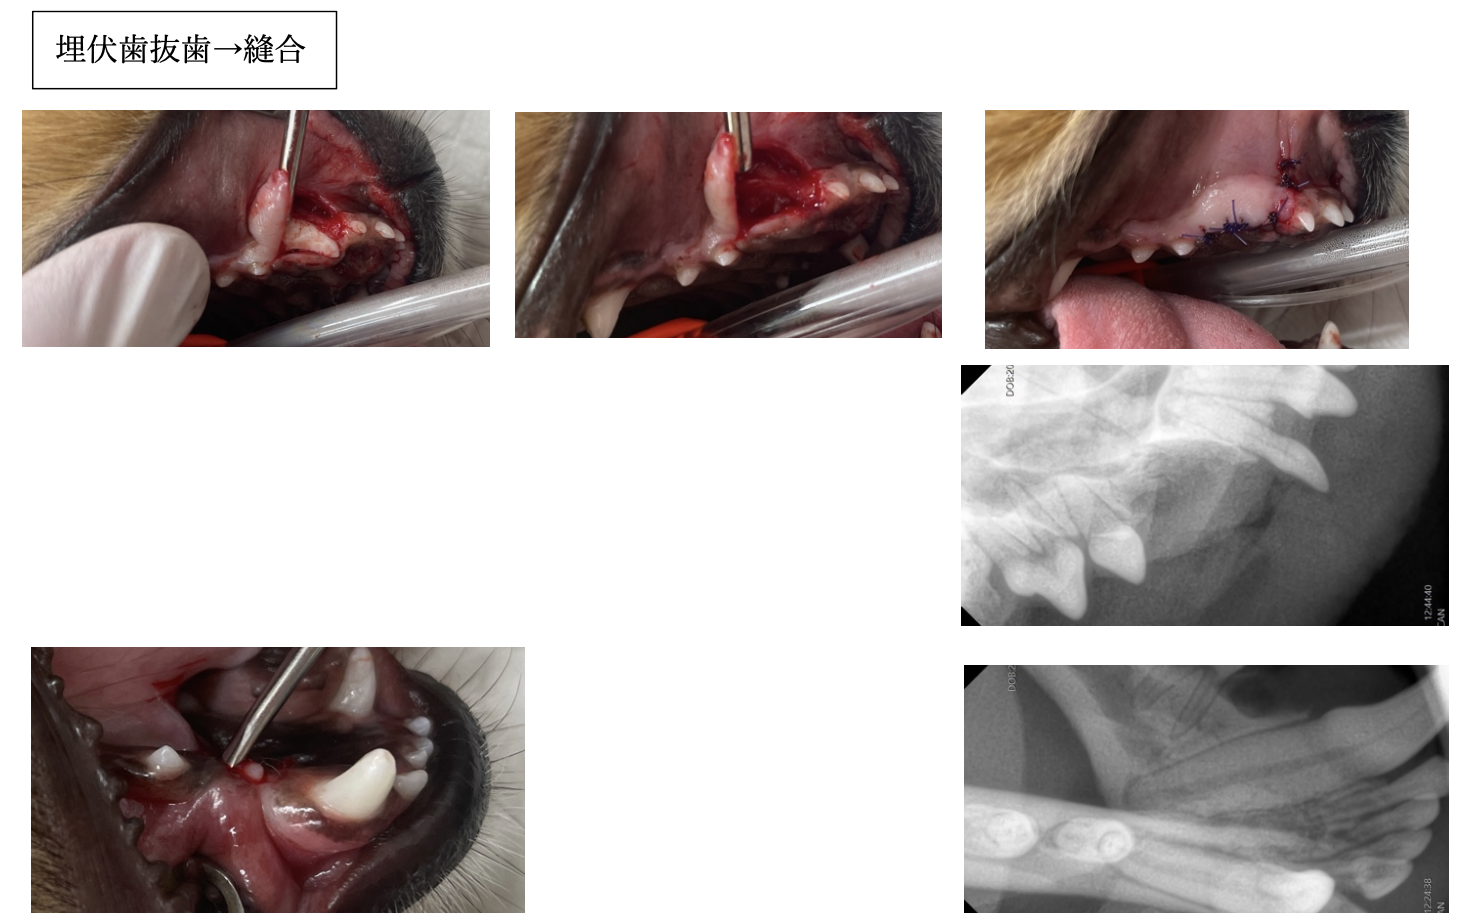

抜歯後、残った歯の一部がないか歯科レントゲン検査も実施します。

半年後に再度検査を実施しました。

抜歯した場所での嚢胞形成はなく、上顎の骨が新たに形成されていました。